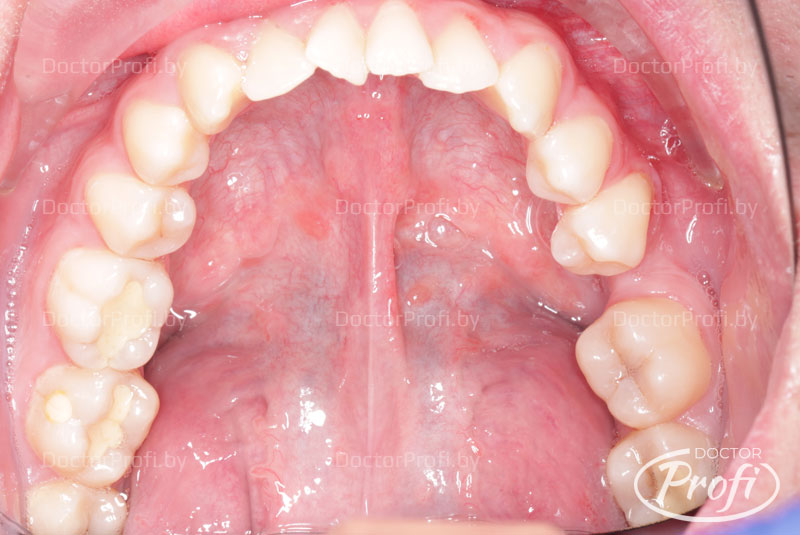

До